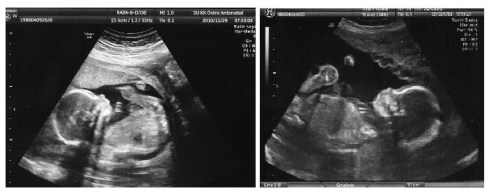

USG

di Swedia, lazimnya USG hanya dilakukan sekali di antara minggu ke 18-20 untuk ibu berusia di bawah 35 tahun. namanya USG morfologi, untuk mengetahui kondisi janin secara detail dan menyeluruh hingga organ-organ dalamnya. kalo semua normal dan tidak ada komplikasi, ya sudah cukup sekali itu aja. kalo mau USG lagi, bisa datang ke private clinic dengan harga yang lumayan. walaupun begitu, untuk usia di atas 35, akan dirujuk juga USG di awal kehamilan (CUB/untuk mendeteksi kemungkinan janin mengalami gejala down syndrome atau tidak). oya, USG nya dilakukan khusus di RS, bukan di tempat biasa kita konsultasi dengan bidan.

entah kenapa, rezeki saya (hehe), baik H1 dan H2 sama-sama di USG 2x! semua kejadiannya setelah saya USG morfologi di RS. waktu H1, ceritanya pas kontrol ke bidan di minggu ke-30an, ada alat USG nangkring di ruangannya. terus bidan saya nawarin, “eh lagi ada alat USG nih, kita intip bayimu yuuukk”. alhamdulillaah.. rezeki. gak perlu bayar bisa dapat USG ke-2 hehe. sementara H2 ini, waktu UK saya 35 minggu, kandungan saya sempat turun. alhasil, untuk ngecek kondisi bayi, saya pun di USG. alhamdulillah gak ada masalah, ya walaupun turunnya kecepetan hehe. tapi jadi rezeki juga kan, dapat USG ke-2 hihi :mrgreen:

kiri: kakakkanan: adik

kiri: kakak

kanan: adik